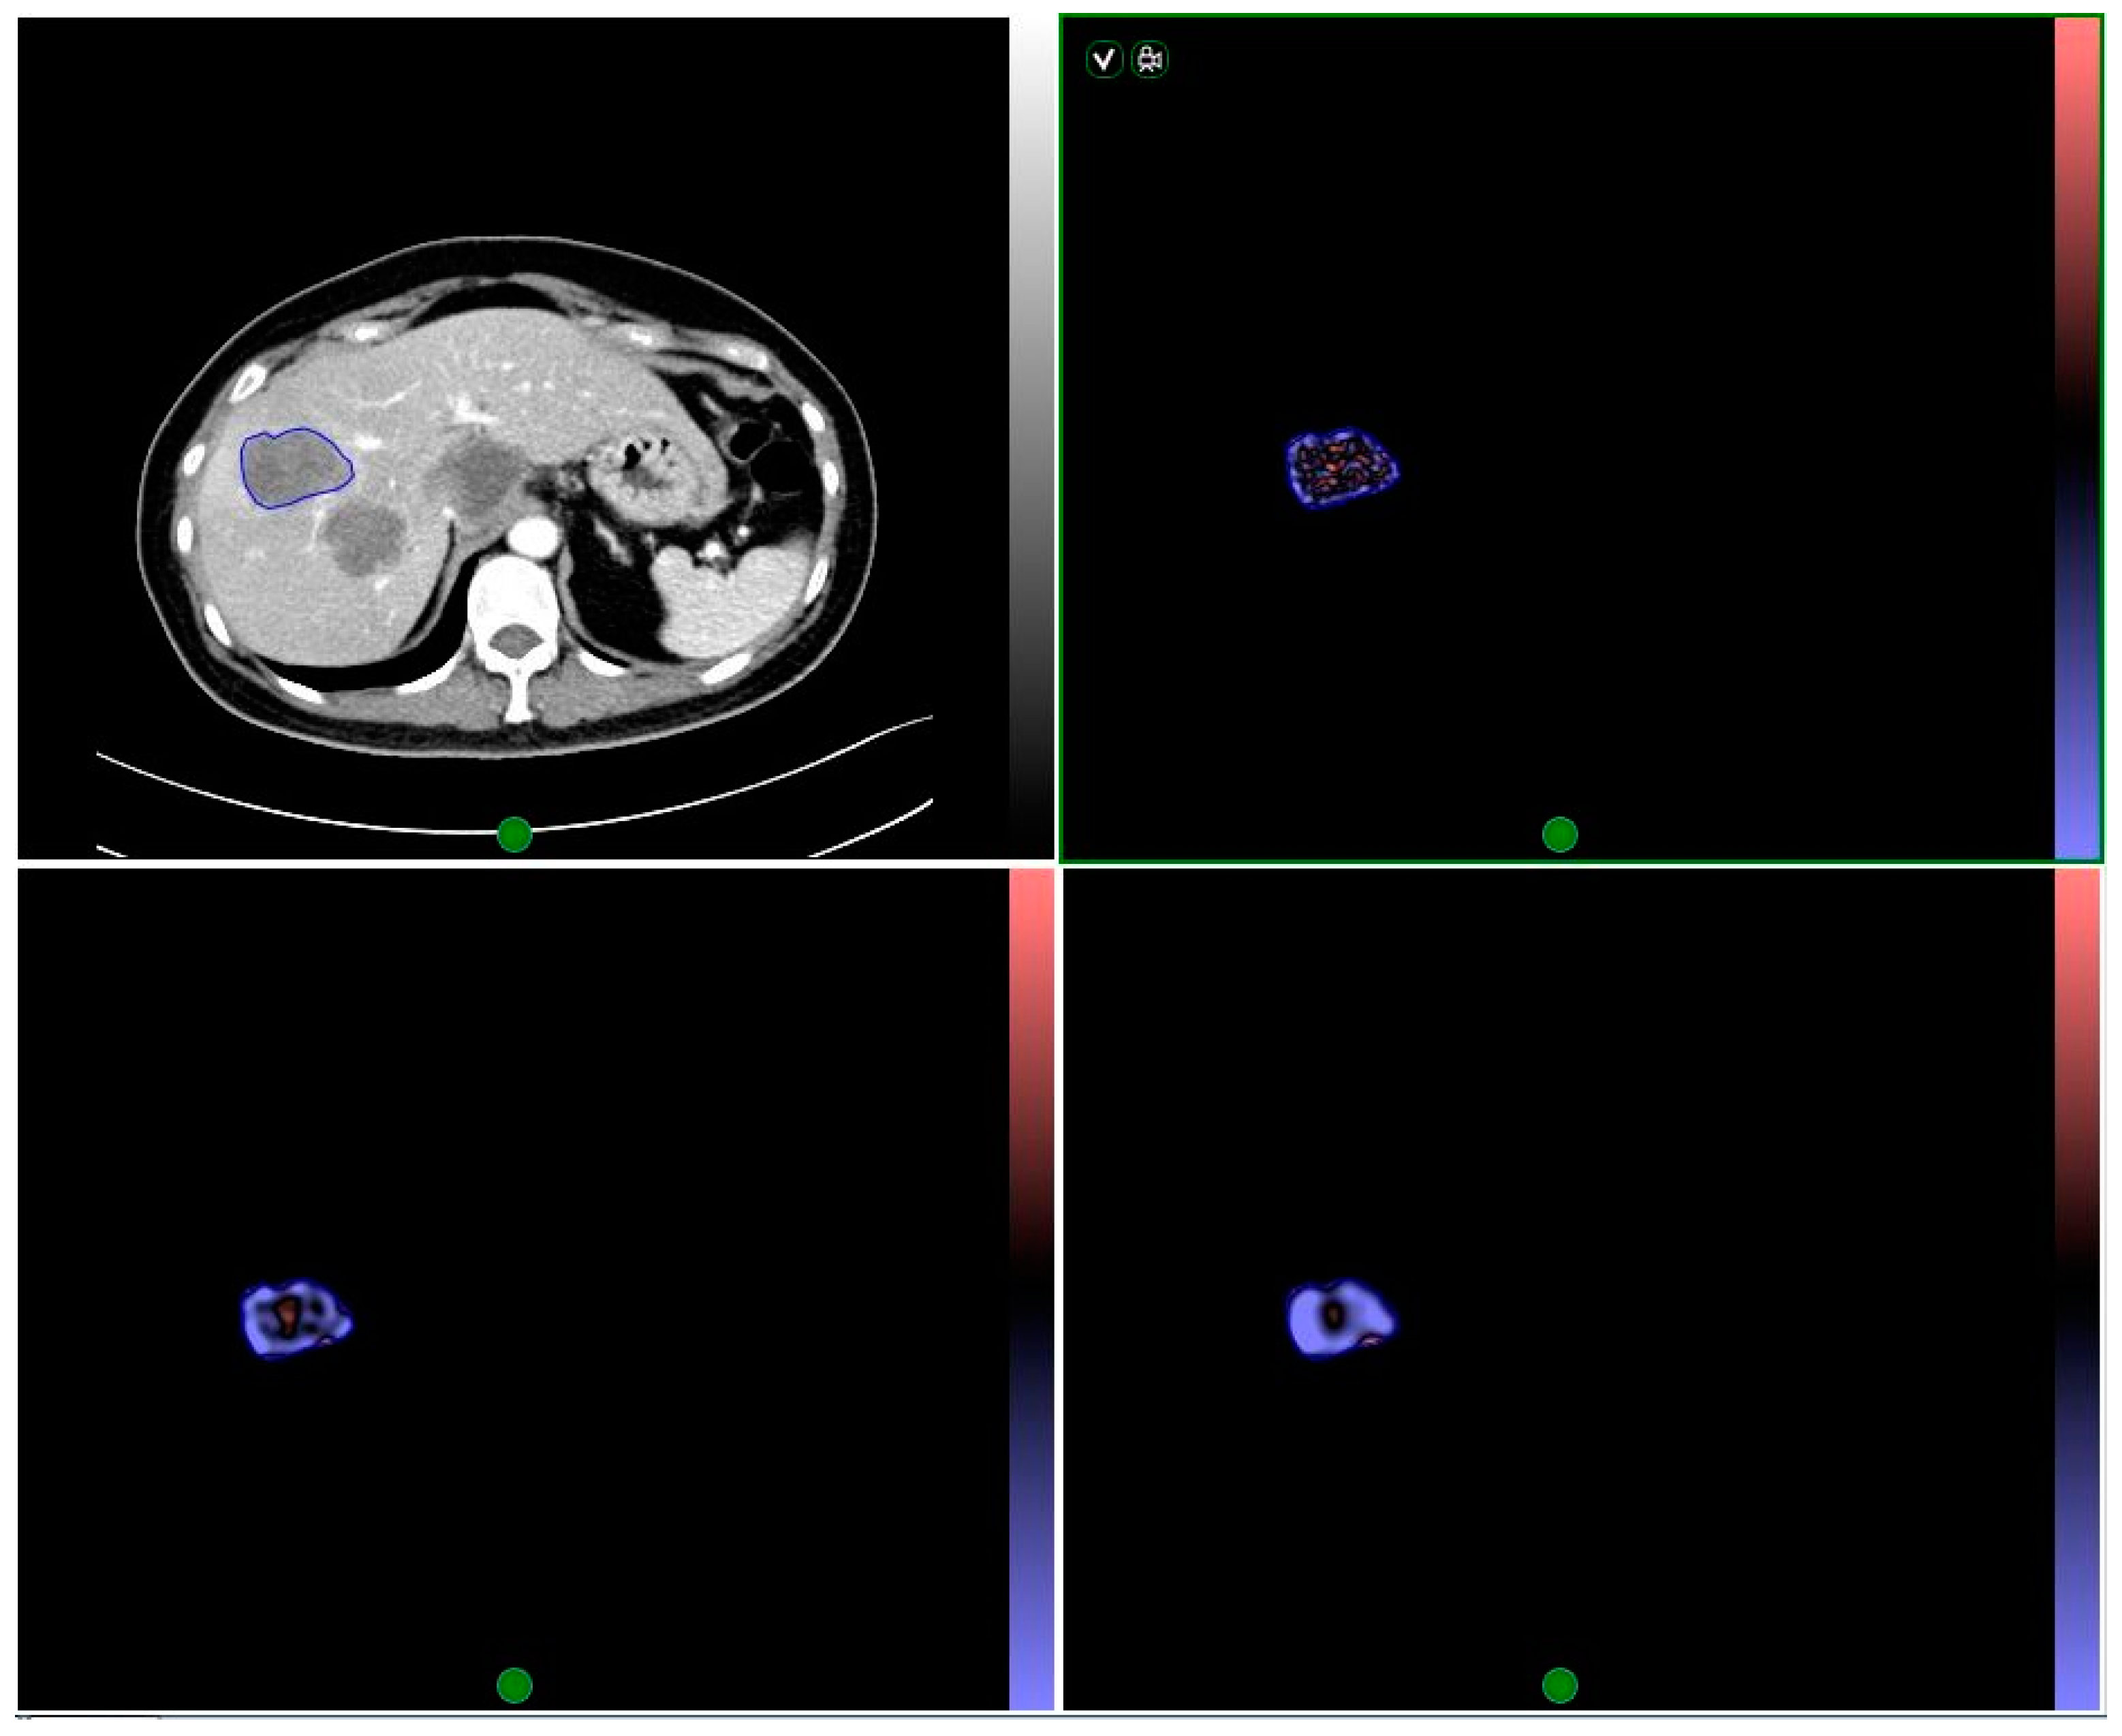

2.4. Texture Analysis

Figure 1. Illustration of lesion delineation, and image filtration at fine, medium, and coarse texture scales.